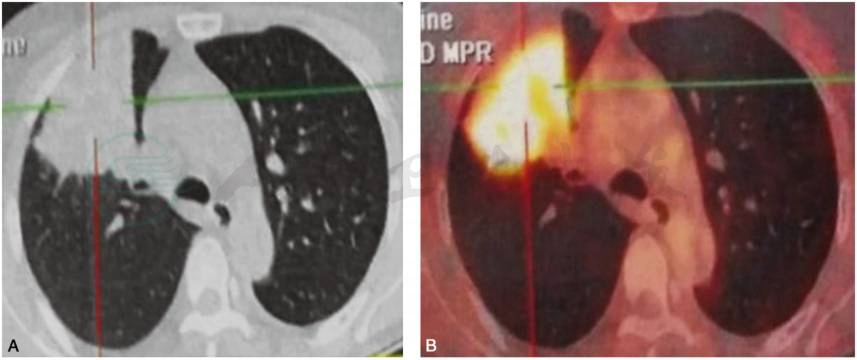

图1 全身PET-CT显像

A.胸部CT扫描示右肺上叶前段实变影;B:PET扫描示右肺上叶前段18-FDG异常高代谢病灶,大小约5.8cm×7.0cm×2.8cm 的实质性肿块(平均 SUV:4.3,最大 SUV:8.5),内密度尚均匀

全身PET-CT显像:右肺上叶前段异常高代谢病灶。

患者病情特点如下:①中年女性患者,以刺激性干咳4个月为主诉;②外院支气管镜检发现右上叶支气管新生物堵塞管腔;③PET-CT发现右肺上叶前段实质性肿块(约5.8cm×7.0cm×2.8cm),内密度尚均匀,最大SUV:8.5。综上,患者需首先考虑肺癌并远端阻塞性肺炎可能。为进一步明确诊断,完善以下检查: